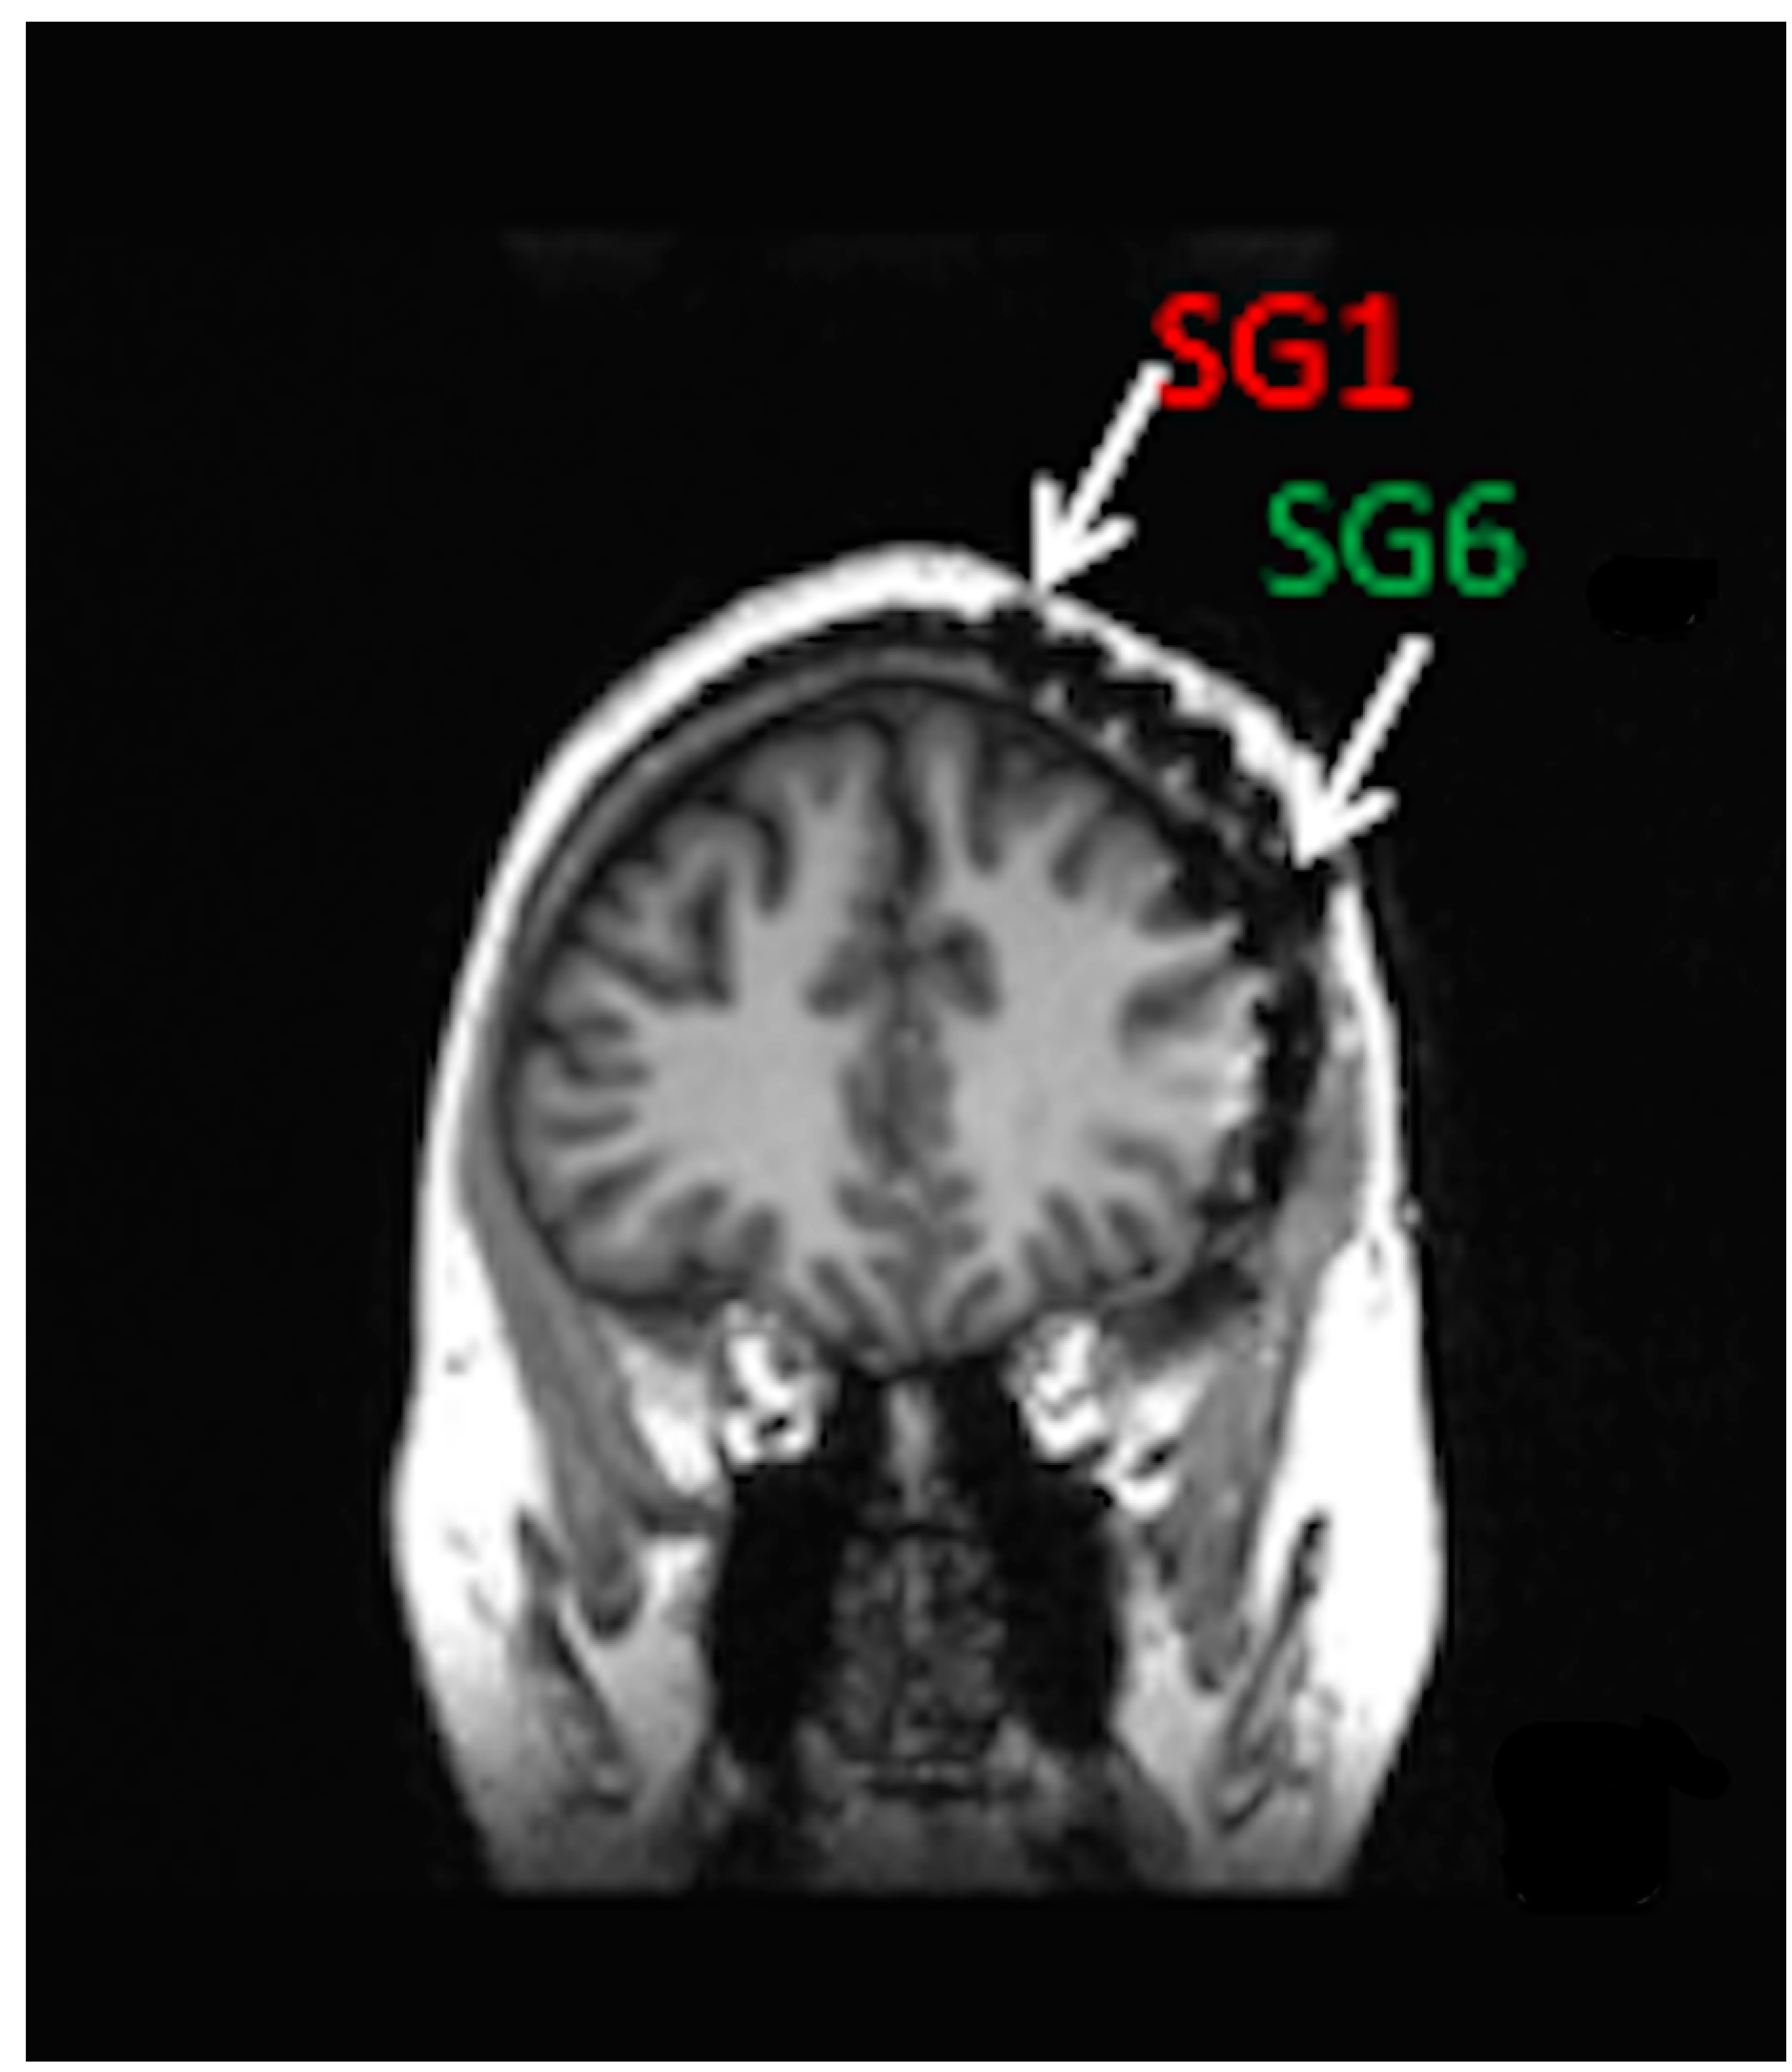

- Haneef, Z.; Yang, K.; Sheth, S.A.; Aloor, F.Z.; Aazhang, B.; Krishnan, V.; Karakas, C. Sub-scalp electroencephalography: A next-generation technique to study human neurophysiology. Clin. Neurophysiol. 2022, 141, 77–87. [Google Scholar] [CrossRef]